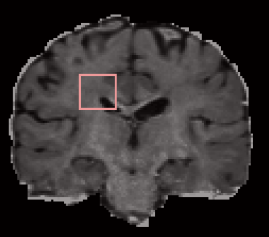

| ROI | CSD |

![]() |

| FORECAST | NODDI-SH |

Figure 9 shows the fODFs obtained by CSD, FORECAST, and NODDI-SH on a region of interest (ROI) of the HCP brain (top left) which includes crossings, fannings, a part of the corpus callosum, and the right ventricle. There are not substantial differences between the three fODFs. The main advantage of using NODDI-SH to calculate the fODF is that it is possible to directly filter out the fODFs which do not belong to white matter. In Figure 9 (bottom right) NODDI-SH fODFs, for instance, only the voxels with were considered for display. In order to do the same with CSD fODFs, it would be necessary to integrate the CSD results with those obtained by a multi-compartmental model, such as NODDI.